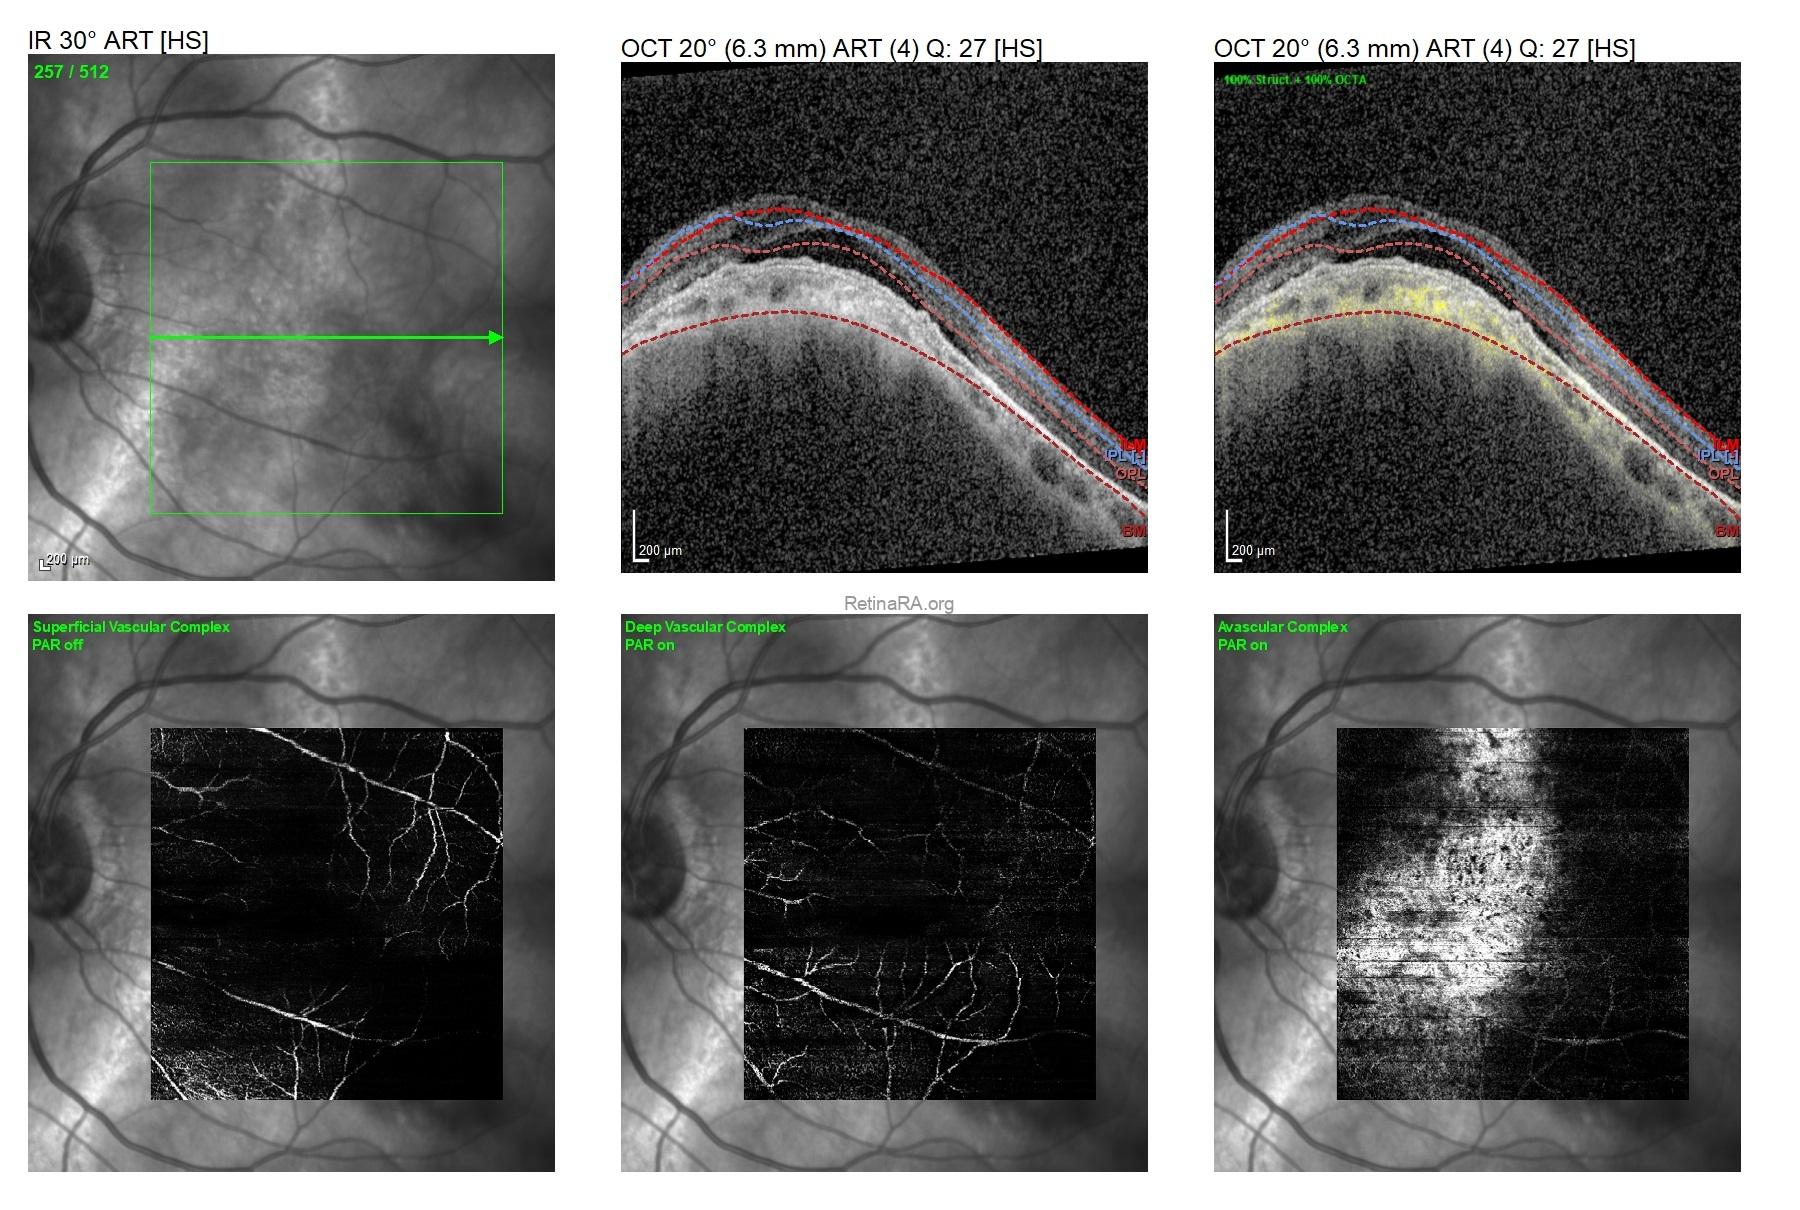

Vertical and horizontal OCT scans of the left eye demonstrated dome-shaped macular configuration with subretinal fluid in addition to shallow pigment epithelial detachment overlying the dome shape.

To rule-out the accompanying macular neovascularization, OCT-A was performed and any neovascular membrane could not detected.